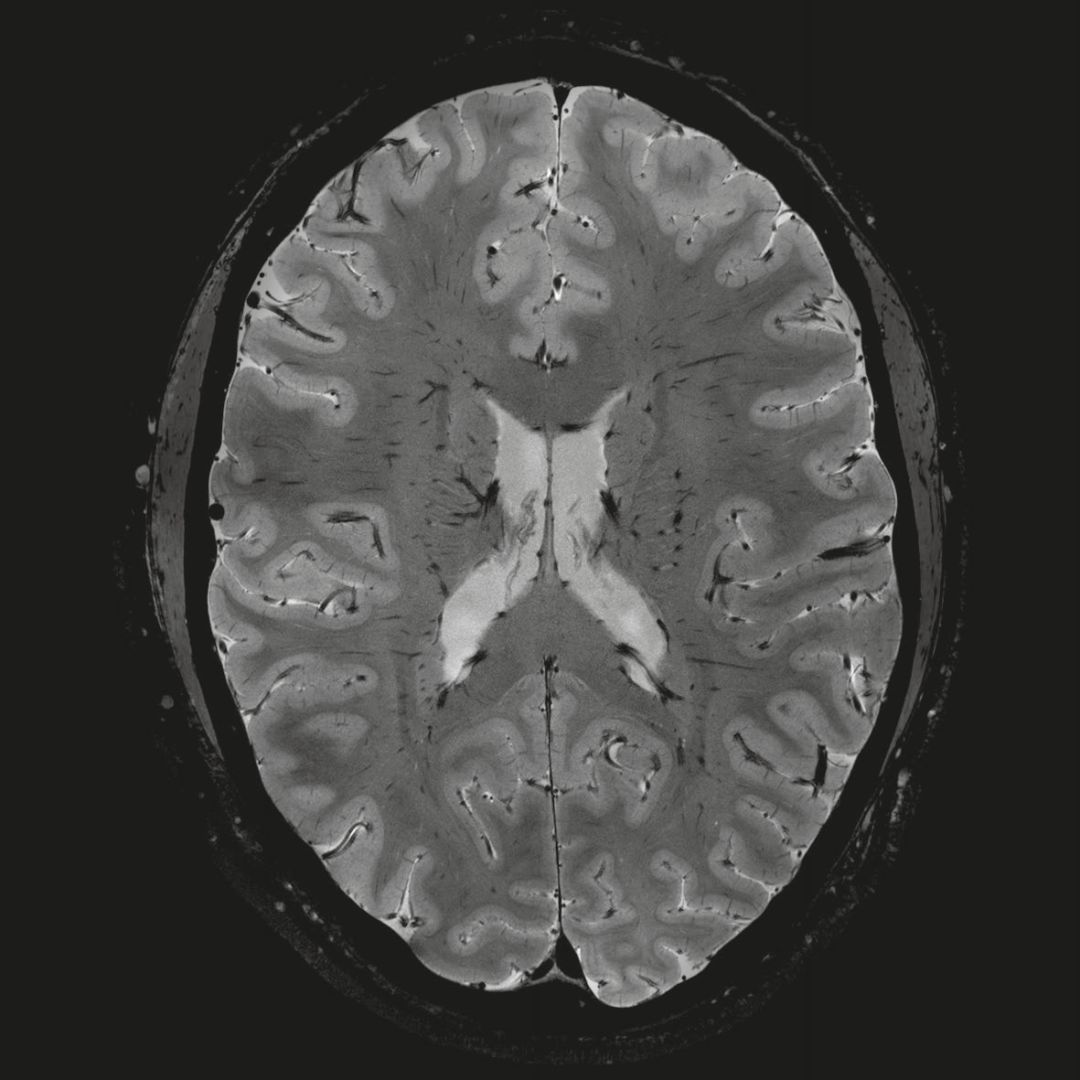

但近年來,西門子與科研機(jī)構(gòu)共同研究發(fā)現(xiàn),7T提供了數(shù)倍于傳統(tǒng)3T磁共振的信噪比和空間分辨率,在神經(jīng)、血管、腫瘤、骨關(guān)節(jié)等多個(gè)方面都會(huì)帶來全新的突破性進(jìn)展。尤其是在目前常規(guī)影像設(shè)備難以診斷的神經(jīng)退行性疾病如阿茲海默氏病、帕金森病等疾病的發(fā)病機(jī)理、早期診斷、治療方案確定以及治療效果評(píng)估上,有著極大的潛力。

MAGNETOM Terra在業(yè)界首次實(shí)現(xiàn)了兩倍于傳統(tǒng)7T的超強(qiáng)梯度性能,實(shí)現(xiàn)超快速、超高效、超高分辨功能磁共振成像。如此高性能的梯度系統(tǒng)無論對(duì)于科研還是臨床都帶來了更多可能。

1毫米的各向同性分辨率DTI:神經(jīng)纖維束的交叉細(xì)節(jié)顯示

0.8毫米的各向同性分辨率:精確劃分灰質(zhì)和白質(zhì)

0.8毫米的各向同性分辨率:超精細(xì)的解剖細(xì)節(jié),例:小腦的精細(xì)結(jié)構(gòu)

超精細(xì)的解剖細(xì)節(jié):T2對(duì)比

0.17 x 0.17 x 0.8毫米分辨率超高。